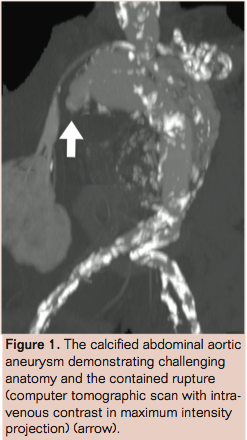

The scan revealed a bilobed, infrarenal aortic aneurysm with a contained, retroperitoneal rupture from the proximal aneurysm toward the patient’s right side (Figure 1). The neck anatomy was high risk for endoleak during EVAR, 5 mm long and angulated 100 degrees (Figure 2).